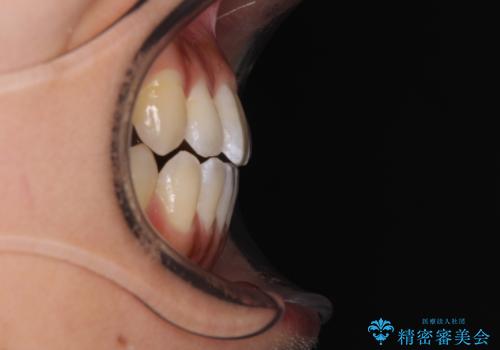

- 前歯の開咬と、上顎前歯の八重歯やデコボコを気にして来院された患者様です。

上顎歯列が狭窄していたため、急速拡大装置により上顎骨を側方に拡大し、その後ワイヤー装置にて矯正治療を行うこととしました。